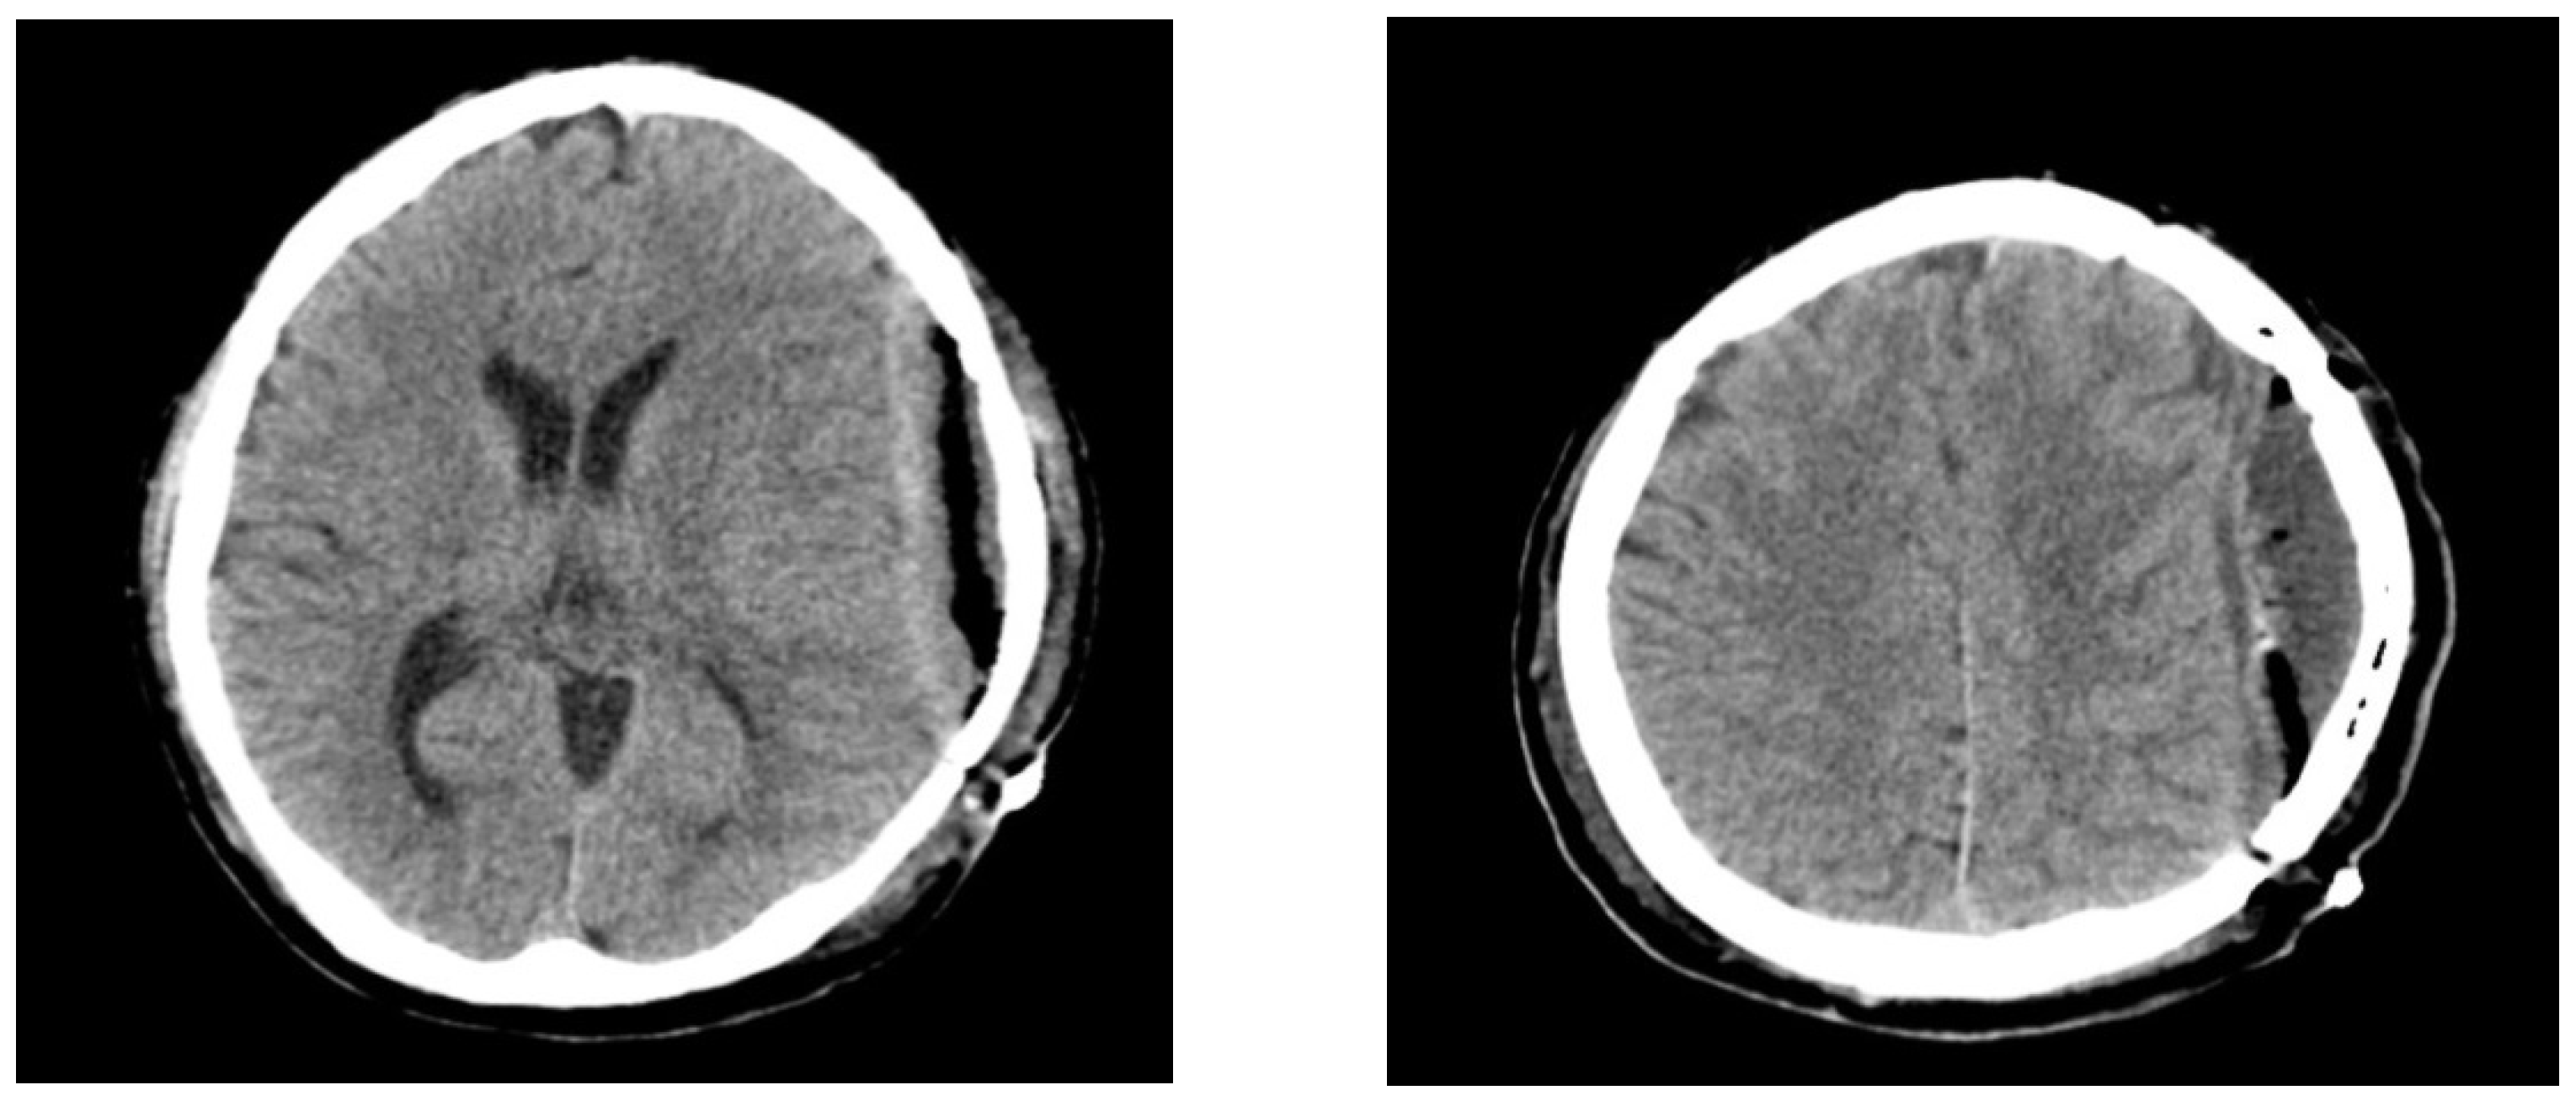

Figure 1. Brain computed tomography scans at 3 months after cranioplasty demonstrate air bubbles and epidural fluid collection. Although cranioplasty is a relatively simple procedure, it carries a substantial risk of postoperative infection or foreign body reaction mimicking infection [1,2] Postoperative infections are usually observed several days to months after cranioplasty operations, and delayed infections presenting 6 years after cranioplasty, as seen in our case, are rare. To the best of our knowledge, no studies have reported aphasia caused by delayed epidural abscess after cranioplasty. A 46-year-old man was admitted to our emergency room (ER) with a complaint of difficulty speaking that started 3 days prior. Left frontotemporoparietal (FTP) craniectomy and hematoma removal were performed for acute subdural hematoma 6 years prior. At 3 months after the decompressive craniectomy, cranioplasty was performed to repair the skull defect using cryopreserved autologous bone. Computed tomography (CT) at 3 months post-cranioplasty revealed postoperative air bubbles and epidural fluid collection (Figure 1).